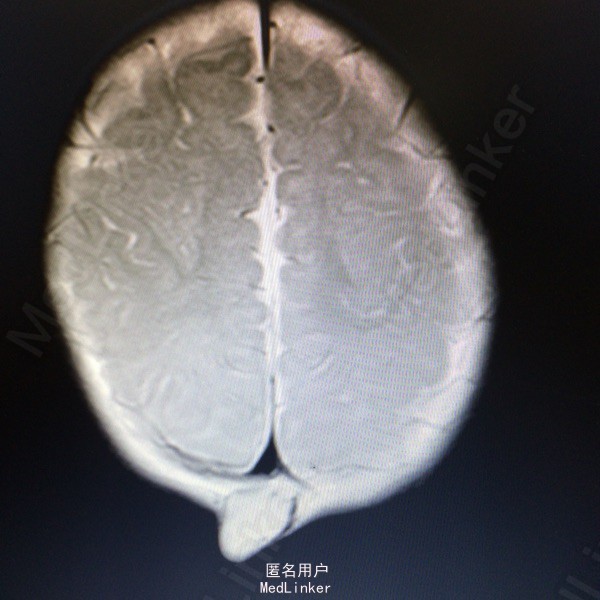

查体:枕后部肿物 辅助检查:行头颅MR提示顶针部中线异常信号,多考虑脑膜膨出

诊断:脑脊膜膨出 处理:枕部脑膜膨出囊切除术➕硬脑膜修补术